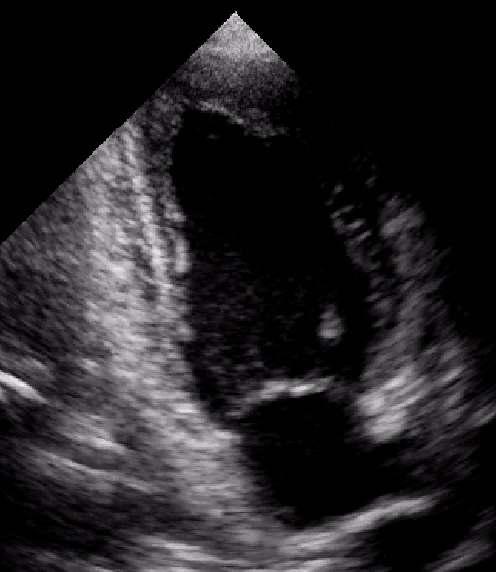

Cardiomiopatia aritmogena

Santo Dellegrottaglie

Oscar Gaddi